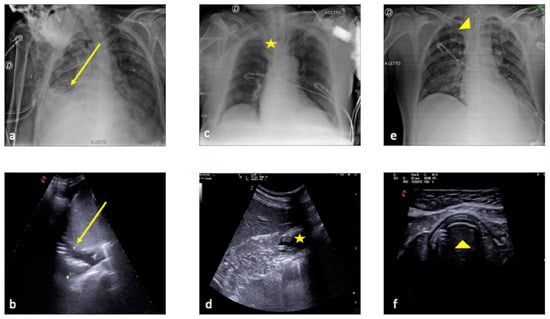

2.1. Atelectasis

2.2. Pneumonia

2.3. Pleural Effusion

2.4. Cardiogenic Pulmonary Edema

2.5. Acute Respiratory Distress Syndrome

2.6. Pulmonary Contusion